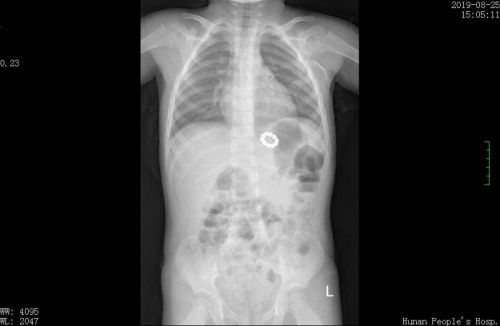

照片复查显示,珠子已被全部取出无金属碎屑残留。

此时,难题摆在医生面前,如果不及时取出这两颗珠子,孩子的胃将被磁力吸穿;如果采用外科手术取出,孩子这么小就要遭受开刀之苦,实在不忍心。杨瑜明教授考虑再三,征得家长同意后,决定利用磁力珠的磁性将珠子“钓”出来。他用手套剪了一个指套,在指套内放入4颗磁力珠系在软管上作为“钓饵”,用胃镜将“钓饵”送至贲门处,嵌入粘膜下组织的2颗磁珠被指套内的磁珠吸引,被拖出体外。复查X片发现,小猛体内没有残余金属碎屑,也没有胃穿孔等并发症,“钓鱼”成功!